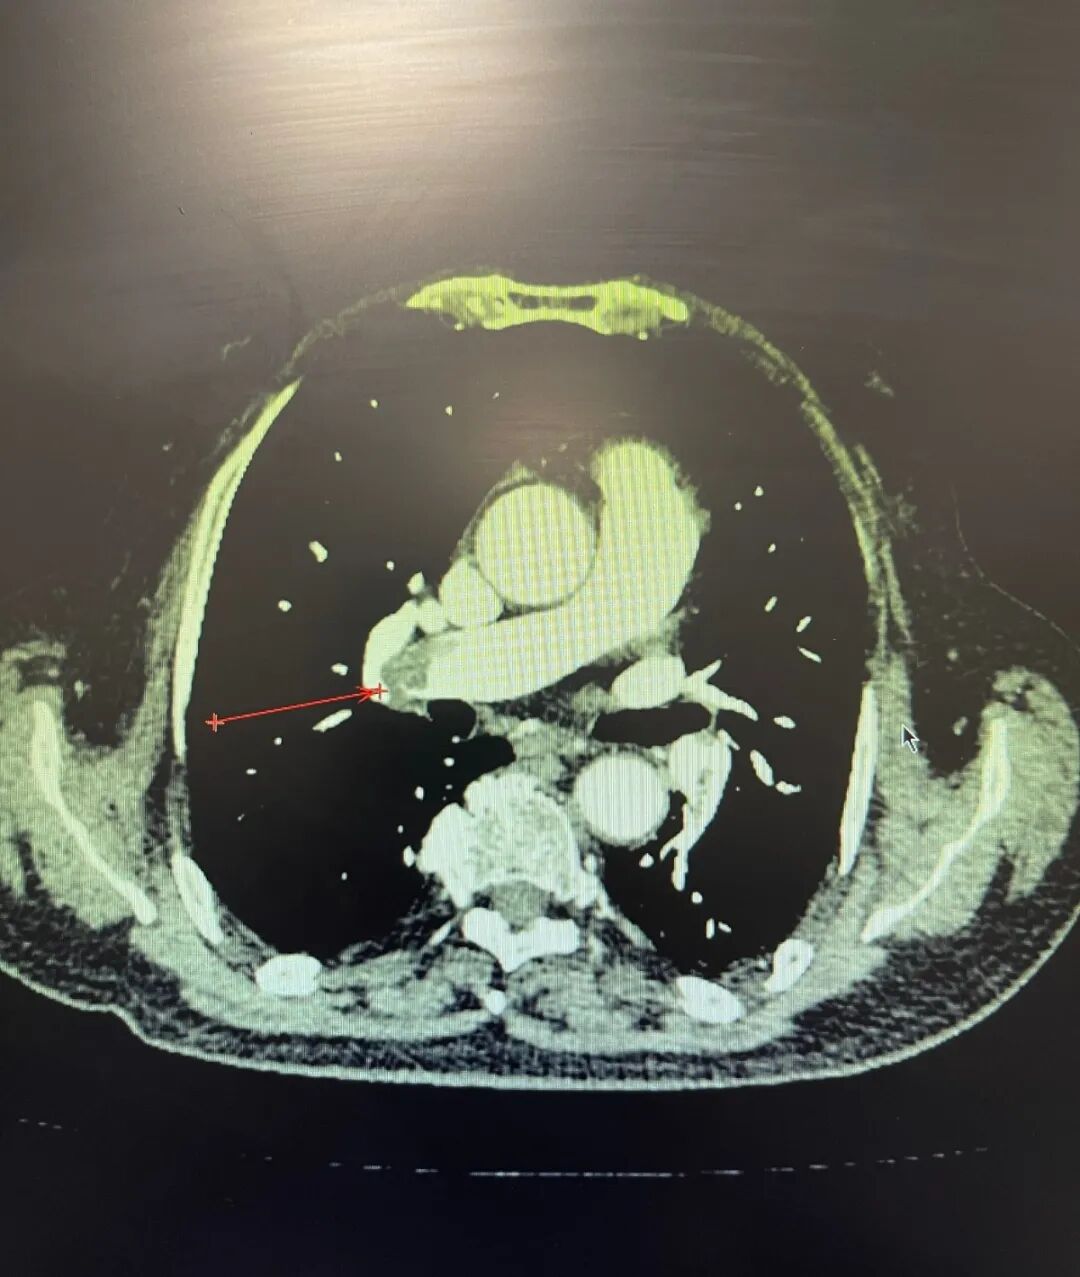

肺动脉CT血管成像清晰地显示,患者双肺动脉主干及几乎所有主要分支,都被大量血栓堵塞。经过紧急而周密的评估,血管外科孙念峰主任团队决定启用前沿介入新技术,使用肺动脉取栓支架为孙阿姨实施手术,解决传统取栓不够彻底的痛点。手术室中,在影像设备引导下,手术团队精准操作。与单纯抽吸或碎栓的导管不同,新技术使用的取栓装置更像一个设计精巧的“网兜”。